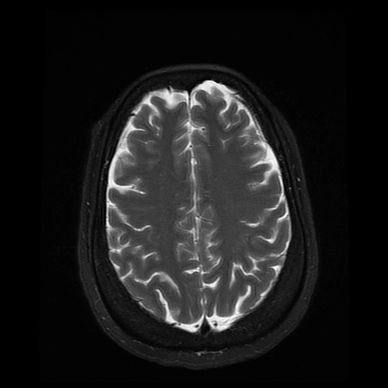

Structural brain damage refers to physical injury or changes to brain tissue that can be seen on brain scans (such as MRI or CT).

In ataxia, this damage most often affects:

🧑⚕️ Diagnosis

Diagnosis usually involves:

- Neurological examination

- Brain imaging (MRI or CT scans)

- Review of medical history and past injuries

- Ongoing monitoring of symptoms

Imaging helps identify where and how much damage is present.